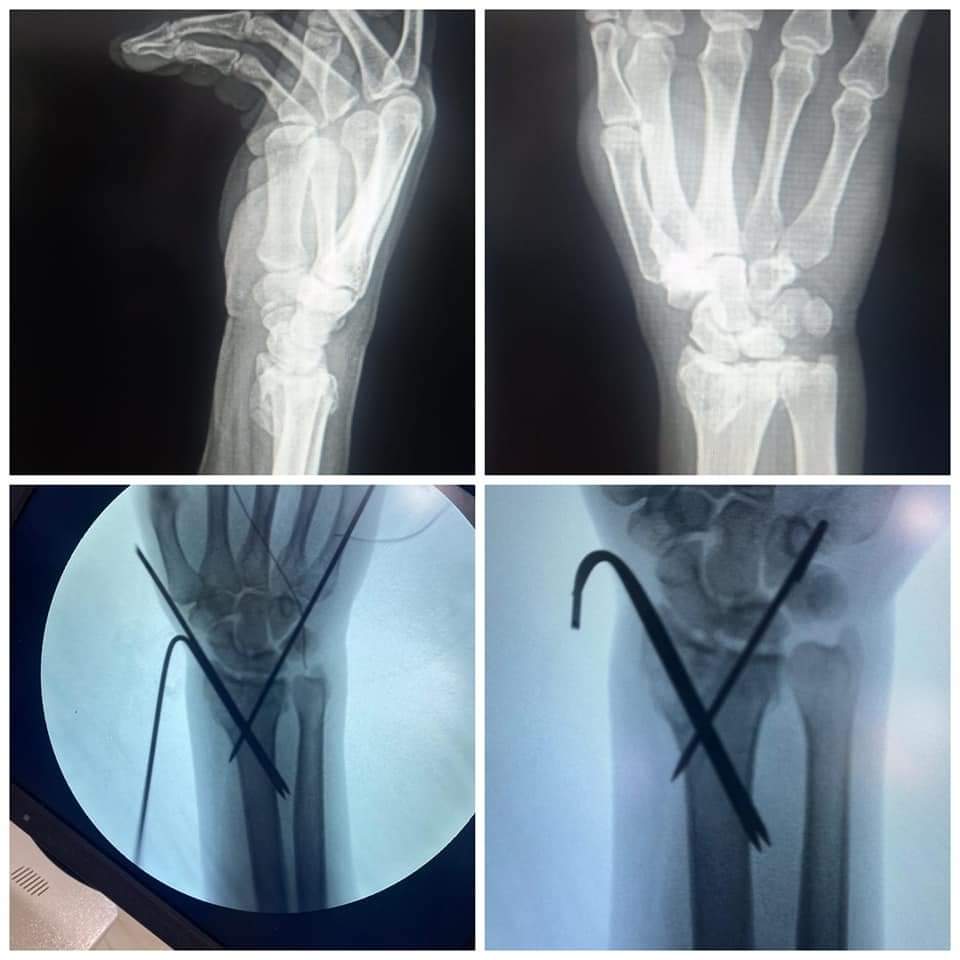

في سياق آخر وتنفيذاً للمبادرة الرئاسية بالقضاء علي قوائم الانتظار الخاصة بالعمليات الجراحية، قام الفريق الطبي بقسم العظام بالمستشفي بإجراء ١٤ عملية جراحية خلال الأسبوع الماضي، وذلك بعد إجراء كافة الفحوصات الطبية والمعملية، والأشعات اللازمة للمرضي، وتنوعت العمليات بين "كبرى، ومتوسطة، وذات مهارة"، لتشمل عملية رد مغلق مع تثبيت كسر مضاعف مفتوح بعظمتي الكعبرة والزند، وعملية رد مغلق مع تثبيت كسر مفتت مفتوح بأعلى النترء البعيد لعظمة العضد، وعملية رد مفتوح مع تثبيت كسر بنهاية عظمة الشظية بالساق بواسطة شريحة ومسامير، وعملية رد مغلق مع تثبيت كسر بمنتصف عظمة القصبة بالساق بمسامير معدنية مرنة، وعملية رد مغلق مع تثبيت كسر بأسفل عظمة الساق بأسلاك معدنية مع رد مفتوح، وتثبيت كسر بأسفل عظمة الشظية، وعملية رد مغلق مع تثبيت بأعلى النتوء البعيد لعظمة العضد، وعملية رد مفتوح مع تثبيت كسر مفتوح مضاعف بعظمة العضد، وعملية رد مغلق مع تثبيت لكسر مفتت مضاعف مفتوح بأسفل عظمة القصبة بالساق بواسطة مثبت خارجي، وعملية إصلاح وتر أكيلس مقطوع كليا، وعملية رد مغلق لخلع متكرر بأصابع القدم، وعملية استخراج جسم غريب من القدم تحت الأشعة المرئية CARM، وعملية تنظيف ورتق وإصلاح جرح متهتك بمنتصف عظمة القصبة بالساق، وعملية رد مغلق مع تثبيت كسر مفتت بالنهاية البعيدة لعظمة الكعبرة....